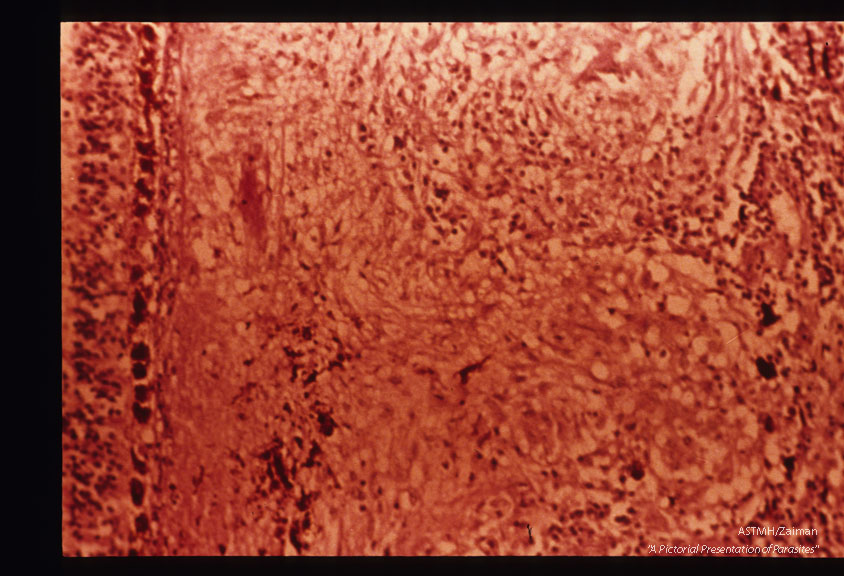

Toxoplasmic retinochoroiditis showing closeup of granulomas in choroid. Organisms were present in retina. Same eye as 1056.

Toxoplasma gondii

Description: Toxoplasmic retinochoroiditis showing closeup of granulomas in choroid. Organisms were present in retina. Same eye as 1056.